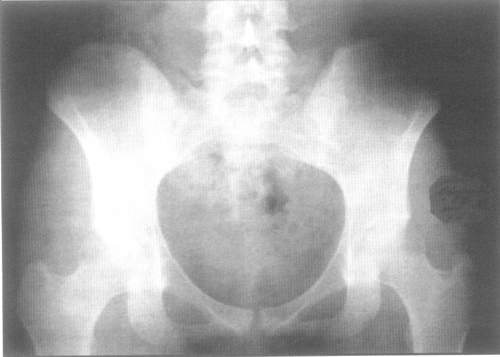

M46.1 Сакроилеит, не классифицированный в других рубриках

Двухсторонний сакроилеит на рентгенограмме